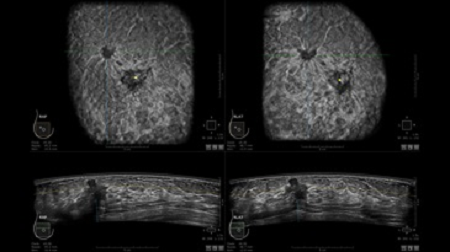

GE INVENIA ABUS – это современный УЗИ аппарат, который создан для точной и эффективной диагностики сканирования с высокой плотностью молочных желез. Выявляемость патологий раковых и предраковых стадий заболевания составляет 55%, что в конечном счете позволяет ставить врачу точные и своевременные диагнозы. Традиционные методы использования маммографии не показывают такой выявляемости, ограничиваясь лишь 3-38%.

УЗИ-аппарат GE INVENIA ABUS позволяет проводить максимально операторонезависимые процедуры, что значительно снижает риск неправильной постановки диагноза и сопутствующие издержки на обработку информации. Система готовит отчет в течение 3-х минут после сканирования, это безусловное преимущество по сравнению с обычным УЗИ сканером.

Определение границ молочной железы (BBD):

Да

Компенсация акустической тени от соска (NSC):

• Алгоритмы обработки изображений: алгоритм однородности изображения ткани (TEA), подавление зернистости, компенсация акустической тени от соска (NSC), определение границ молочной железы (BBD), определение стенки грудной клетки

• Отображение объемных 3D ультразвуковых изображений, которые состоят из традиционных поперечных и воссозданных коронарных и сагиттальных проекций

• Стандартизованная ориентация изображения: «толстый срез» в коронарной плоскости; поперечная; сагиттальная плоскость; радиальный и антирадиальный поворот изображения; просмотр исключительно области интереса